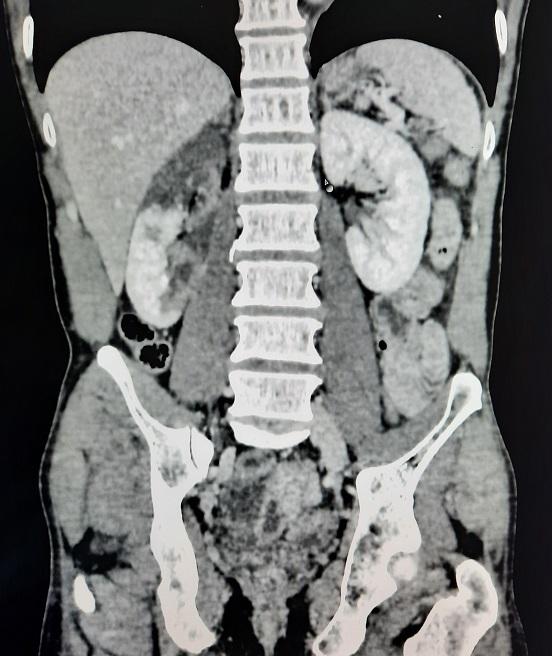

Le médecin prescrit un bilan sanguin, et un uroscanner dont les résultats sont disponibles

Scanner montre une dissection aortique de type B avec embole rénale

Appel du chirurgien vasculaire du C.H.U. de secteur : pas d’indication chirurgicale ni de thrombolyse pour le moment.

Transfert en chirurgie thoracique